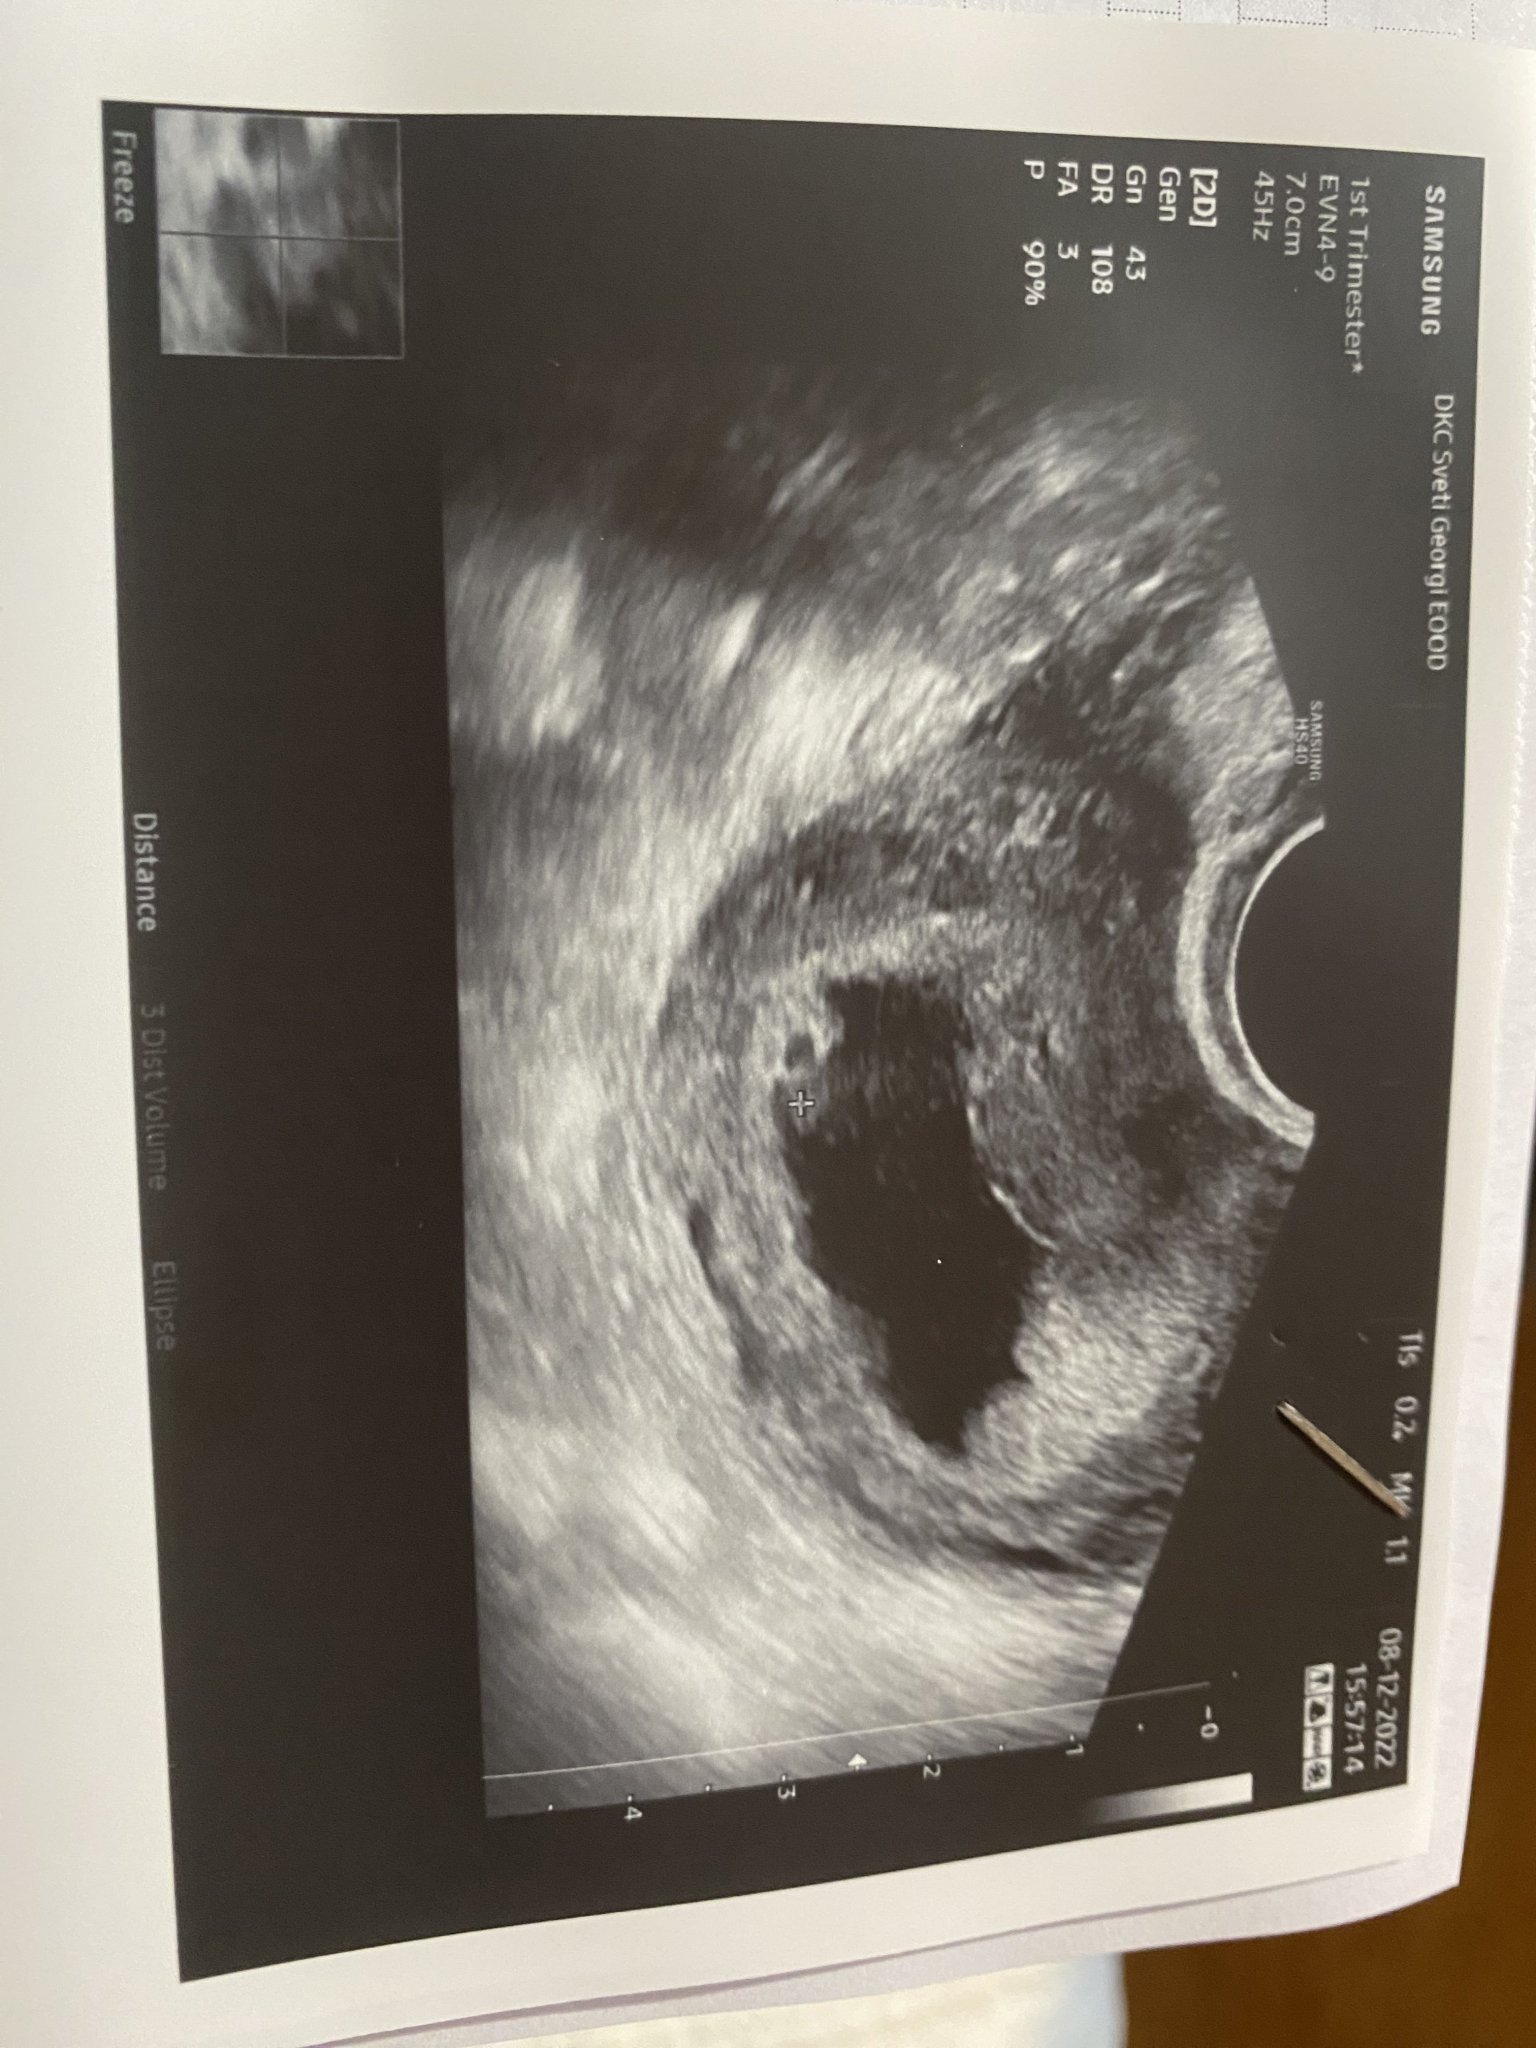

Какво представлява изображението от ехографията на 5-седмична и 2-дневна бременност?

Какво представляват белите точки в плодния сак на ехографската снимка?

щом лекар е видял бременност, някой от форума едва ли ще види нещо друго. Според мен това може да е малко сакче, но и не съм и лекар. Не сте ли правила тест за бременност? Направете един.